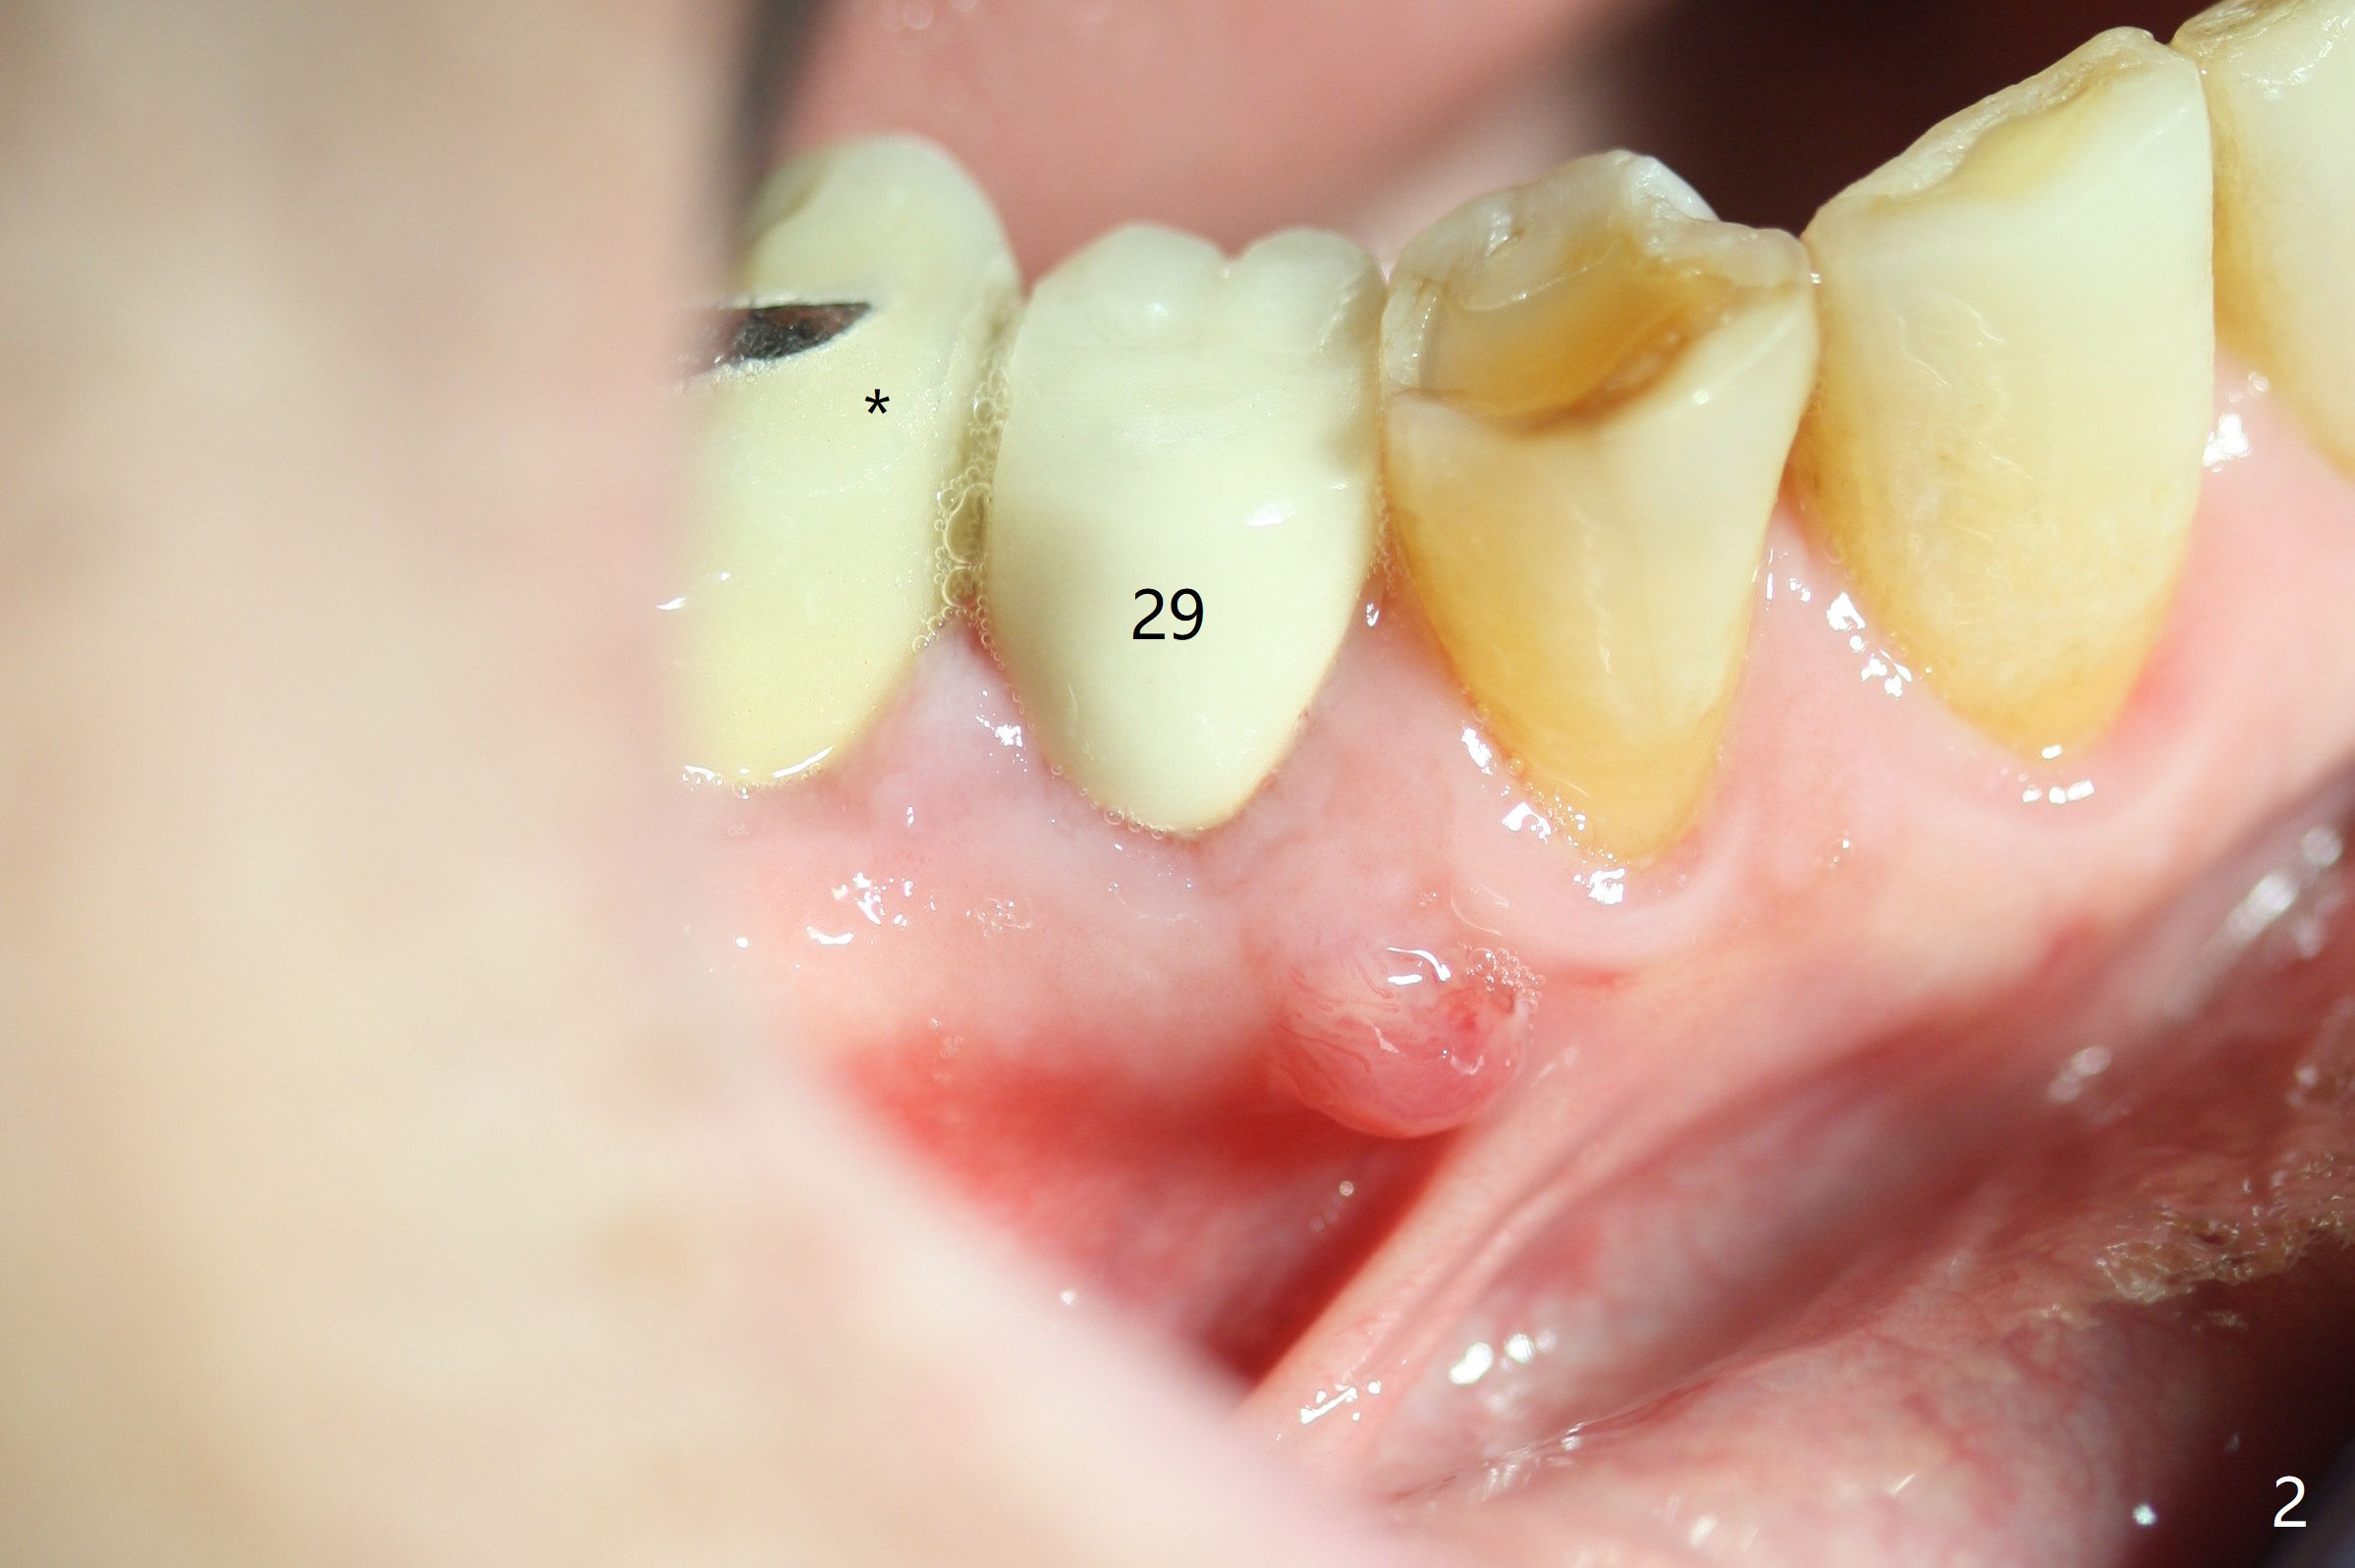

While the guided implant at #19 is osteointegrating, porcelain chips in the mesial marginal ridge of the retainer at #30 (Fig.2 *), causing food impaction between #29 and 30. The units #30 and 31 are removed. Impression is taken for guide at #31 (Fig.1). A temporary crown is fabricated for #30. Since there is sufficient bone, a 5x11.5 mm implant will be placed (Fig.1). If mouth opening is limited, a 10 mm long will be used. RCT will be done for the tooth #29 first for the buccal fistula (Fig.2). The fistula disappears 1 month post RCT (Fig.3,4 <) when a 5x10 mm implant is placed at #31.